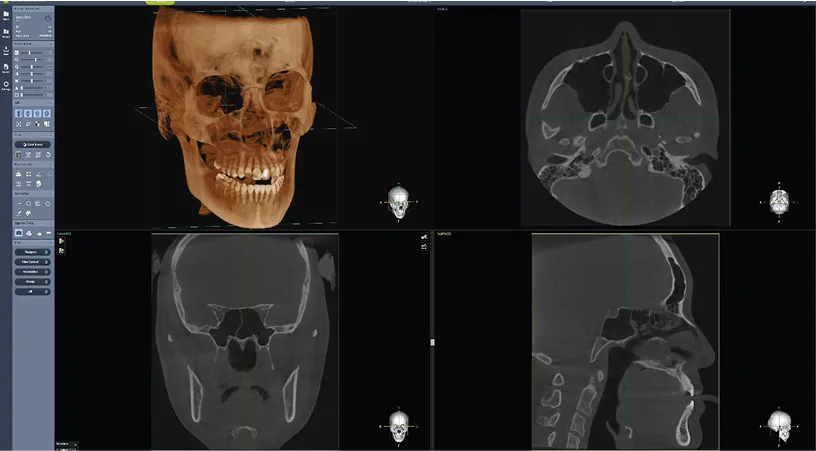

Analiza tridimensională completă este realizată prin reconstrucții multiplanare (MPR – axial, sagital, coronal), secțiuni transversale (cross-sectional) și vizualizare volumetrică 3D, oferind o perspectivă corectă asupra volumului osos și a relațiilor anatomice. În implantologie, aceste funcționalități permit poziționarea implantului atât din punct de vedere chirurgical, cât și protetic, reducând discrepanțele dintre planificare și execuție și transformând tratamentul într-un proces predictibil.

Un rol central îl are software-ul Dentium (Rainbow 3D Viewer + Image Viewer), care integrează funcții avansate într-o interfață intuitivă. Acesta permite reconstrucții MPR, analiză volumetrică 3D, măsurători precise și planificare chirurgicală, optimizând fluxul de lucru și reducând timpul necesar pentru interpretare. În practică, acest lucru se traduce prin eficiență crescută, reproducibilitate și integrare reală în rutina clinică.